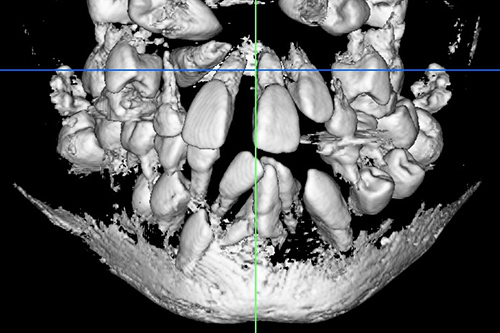

CT検査

3次元情報から、歯の位置・埋伏歯(歯冠の全てまたは一部が顎の骨や歯肉の中に埋まって出ていない歯)・過剰歯(決まった本数よりも多く歯が生えてくること)などを確認します。埋伏歯や過剰歯があると、歯が移動する際に適切な動きができなくなってしまうため、事前に不要な歯を確認しておく必要があります。また歯の移動に大きく関係する骨の厚さや距離などの情報も得られ、精度の高い矯正治療のための重要な情報源を採取することができます。

埋伏歯の位置や方向が確認できる

CT検査の例

CT検査で確認できる軸位断図

CTを使用すると、左記の軸位断図のように様々な角度の断面から歯の位置などの確認をすることができます。

3D構築画像

アキシャル像

コロナル像

サジタル像

※症例に合わせて必要な場合にのみCT検査を行います。

※医療連携している医院で撮影させていただきます。